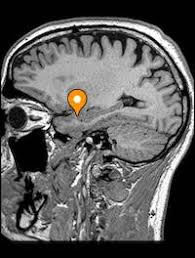

Quando uma pessoa sente ódio, várias áreas do cérebro são ativadas, incluindo a amígdala, que desempenha um papel central no processamento de emoções, especialmente as regiões do medo e da raiva.

Os corpos amigdaloides do cérebro desencadeiam uma cascata de reações químicas e atividades neurais que resultam na liberação dos neurotransmissores noradrenalina e dopamina, que estão relacionadas à excitação, alerta e reações de luta ou fuga. Essas substâncias químicas podem intensificar o sentimento de ódio e aumentar a disposição para agir de forma agressiva.

Além disso, outras áreas do cérebro, como o Córtex Pré-frontal (PFC), estão envolvidas no processamento do ódio: tendo como função a inibição de impulsos primários vindos do nosso ‘cérebro animal’, o sistema límbico, é a região Pré-frontal que acaba nos dando o controle emocional, e também ajuda na tomada de decisões – atacar, proteger ou fugir – bem como na regulação e na modulação da intensidade do comportamento.

Em situações de ódio intenso, essa região pode ser parcialmente ou totalmente inibida, diminuindo, assim, a capacidade de reflexão e de moderação necessárias para o planejamento e execução de uma ação. Quando ocorre dentro de uma situação de alta intensidade emocional, este cenário neuropsicológico poderá levar uma pessoa a agir de forma destrutiva com pouco ou nenhum autocontrole.

Córtex pré-frontal medial: O córtex pré-frontal medial, incluindo a área conhecida como córtex cingulado anterior, desempenha um papel na regulação emocional e no processamento de informações sociais complexas. Essa região está envolvida na avaliação de ameaças interpessoais e na regulação das respostas emocionais relacionadas ao ciúme.

Núcleo estriado: O núcleo estriado está envolvido no processamento de recompensa e motivação. Estudos sugerem que essa região desempenha um papel na resposta de recompensa associada à exclusividade e posse em relacionamentos amorosos, que estão relacionados ao ciúme romântico.

Córtex pré-frontal dorsolateral: O córtex pré-frontal dorsolateral está envolvido na regulação cognitiva e no controle inibitório. Essa região desempenha um papel importante na modulação dos pensamentos e comportamentos associados ao ciúme, ajudando a controlar impulsos e reações automáticas.

Principais regiões encefálicas ativadas durante o sentimento do ciúmes.

Corpos amigdaloides

Córtex Prefrontal

Giro do Cíngulo completo

Porção anterior do Giro do Cíngulo

Núcleo Estriado